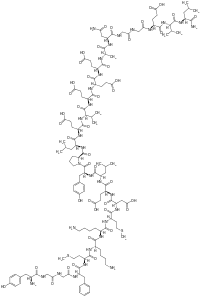

| Opioid peptides | Skeletal molecular images |

| Adrenorphin |  |

| Amidorphin |  |

| Casomorphin | |

| DADLE | |

| DAMGO |  |

| Dermorphin | |

| Endomorphin |  |

| Morphiceptin |  |

| Nociceptin |  |

| Octreotide |  |

| Opiorphin |  |

| TRIMU 5 |  |